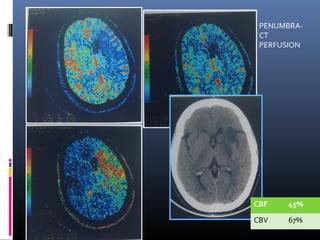

CT PERFUSION

CBF 30%

CBV 54%

PENUMBRA-

CT

PERFUSION

CBF 45%

CBV 67%